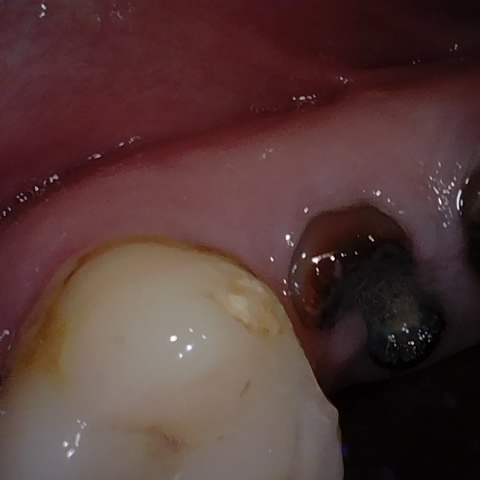

Annotated as "Good"